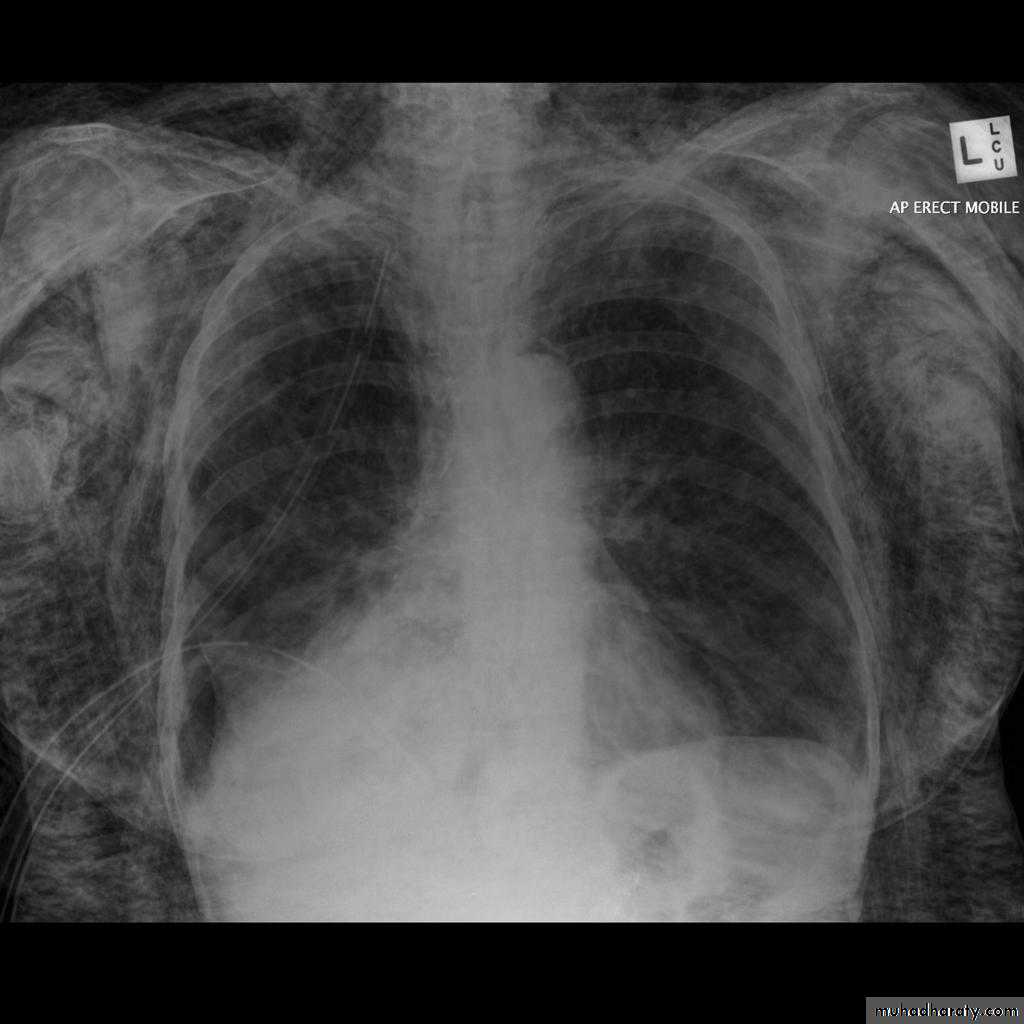

Plain radiographChest radiographs are the most commonly used examination to assess for presence of a pleural effusion, however it should be noted that on a routine erect chest x-ray as much as 250-600 ml of fluid is required before it becomes evident 6. A lateral decubitus film is most sensitive, able to identify even a small amount of fluid. At the other extreme, supine films can mask large quantities of fluid.

Both PA and AP erect films are insensitive to small amounts of fluid. Features include:

blunting of the costophrenic angle

blunting of the cardiophrenic angle

fluid within the horizontal or oblique fissures

eventually a meniscus will be seen, on frontal films seen laterally and gently sloping medially (note:

with large volume effusions, mediastinal shift occurs away from the effusion (note: if coexistent collapse dominates then mediastinal shift may occur towards the effusion)